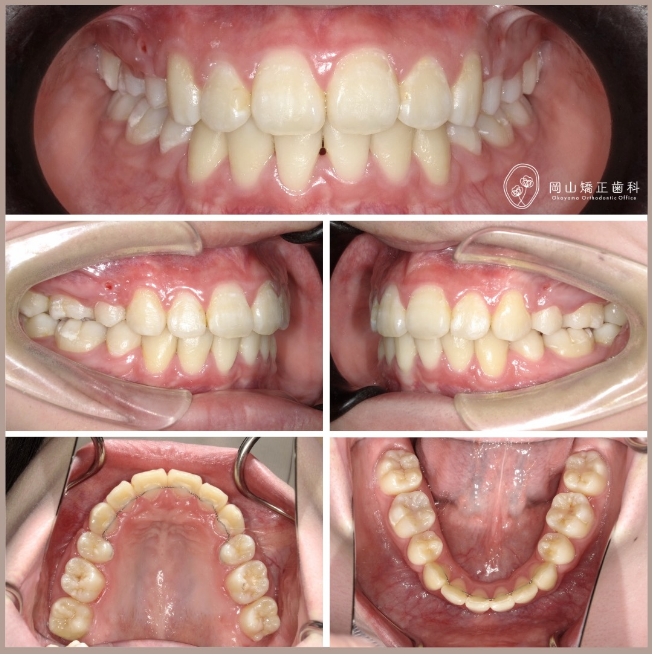

症例01

| 年齢 | 17歳 |

|---|---|

| 住所 | 岡山県総社市 |

| 主訴 | 出っ歯が気になる |

| 診断名 | 叢生と過蓋咬合を伴う上顎前突症例 |

| 治療装置 | マルチブラケット矯正装置(ワイヤー矯正) |

| 抜歯部位 | 上顎両側第1小臼歯、下顎両側第1小臼歯 |

| 治療期間 | 2年11ヶ月 |

| 費用 | 約85万円 |

| リスク | 痛み、歯肉退縮、歯根吸収など |